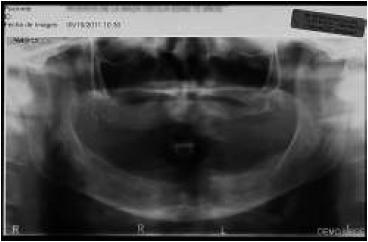

La planificación se realizó por medio de una ortopantomografía (fig. 5), evitando la utilización de cone-beam, siguiendo nuestro objetivo de realizar un tratamiento con un bajo costo. Al momento de la cirugía la paciente se encontraba premedicada con amoxicilina de 500 mg cada 8 h desde el día anterior15,16, ibuprofeno 400 mg cada 8 h10, comenzando 1 h antes de la cirugía17 y colutorios de clorhexidina al 0,12%, habiendo iniciado el tratamiento 48 h antes del procedimiento quirúrgico4. En el pabellón se probó nuevamente la guía multifuncional en boca (fig. 6), se anestesió a la paciente para luego realizar una incisión crestal desde la zona del primer molar derecho a la zona del primer molar izquierdo10,15,18, con incisiones liberadoras bilaterales, para luego realizar la disección subperióstica lingual y vestibular18. Con la plantilla radiográfica proporcionada por el fabricante se seleccionó sobre la radiografía panorámica el largo de los implantes a colocar. La cantidad de tejido óseo en sentido vestíbulo-lingual observada durante la cirugía fue de 5-6 mm, por lo que los implantes utilizados fueron implantes cónicos Strong SW de hexágono interno (SIN®, Sao Paulo, Brasil) de 3,8 mm de diámetro. Con la ayuda de la guía como referencia, se colocó 2 implantes distales, uno en cada lado, en la zona de los primeros premolares, inclinados a distal5, teniendo una longitud de 13 mm. Otros 2 implantes se colocaron a cada lado de la línea media mandibular, con una longitud de 15 mm. Se comprobó que los 4 implantes tuviesen una estabilidad primaria superior a los 30 N/cm (fig. 7). Se instalaron pilares Mini-Abutment y cilindros de protección de pilar, también teniendo como referencia la guía multifuncional. Se eligió suturar los tejidos con sutura no reabsorbible 4-018,19 (Seda, Ethicon, Johnson & Johnson, Brasil), siguiendo nuestro objetivo de disminuir los costos del procedimiento, y se envió a la paciente a la sala de recuperación (fig. 8).